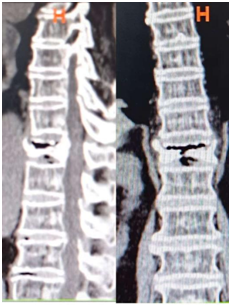

现在常用的是微创骨水泥手术,刘老太就是接受了这种治疗。骨科一病区科主任徐明杰和张鹏飞主治医生往她骨折的椎体里注入了一种叫“骨水泥”的材料,凝固后就能把压扁的骨头撑起来,快速稳定脊柱、缓解疼痛。

▲ 术前CT

▲ 术后X线